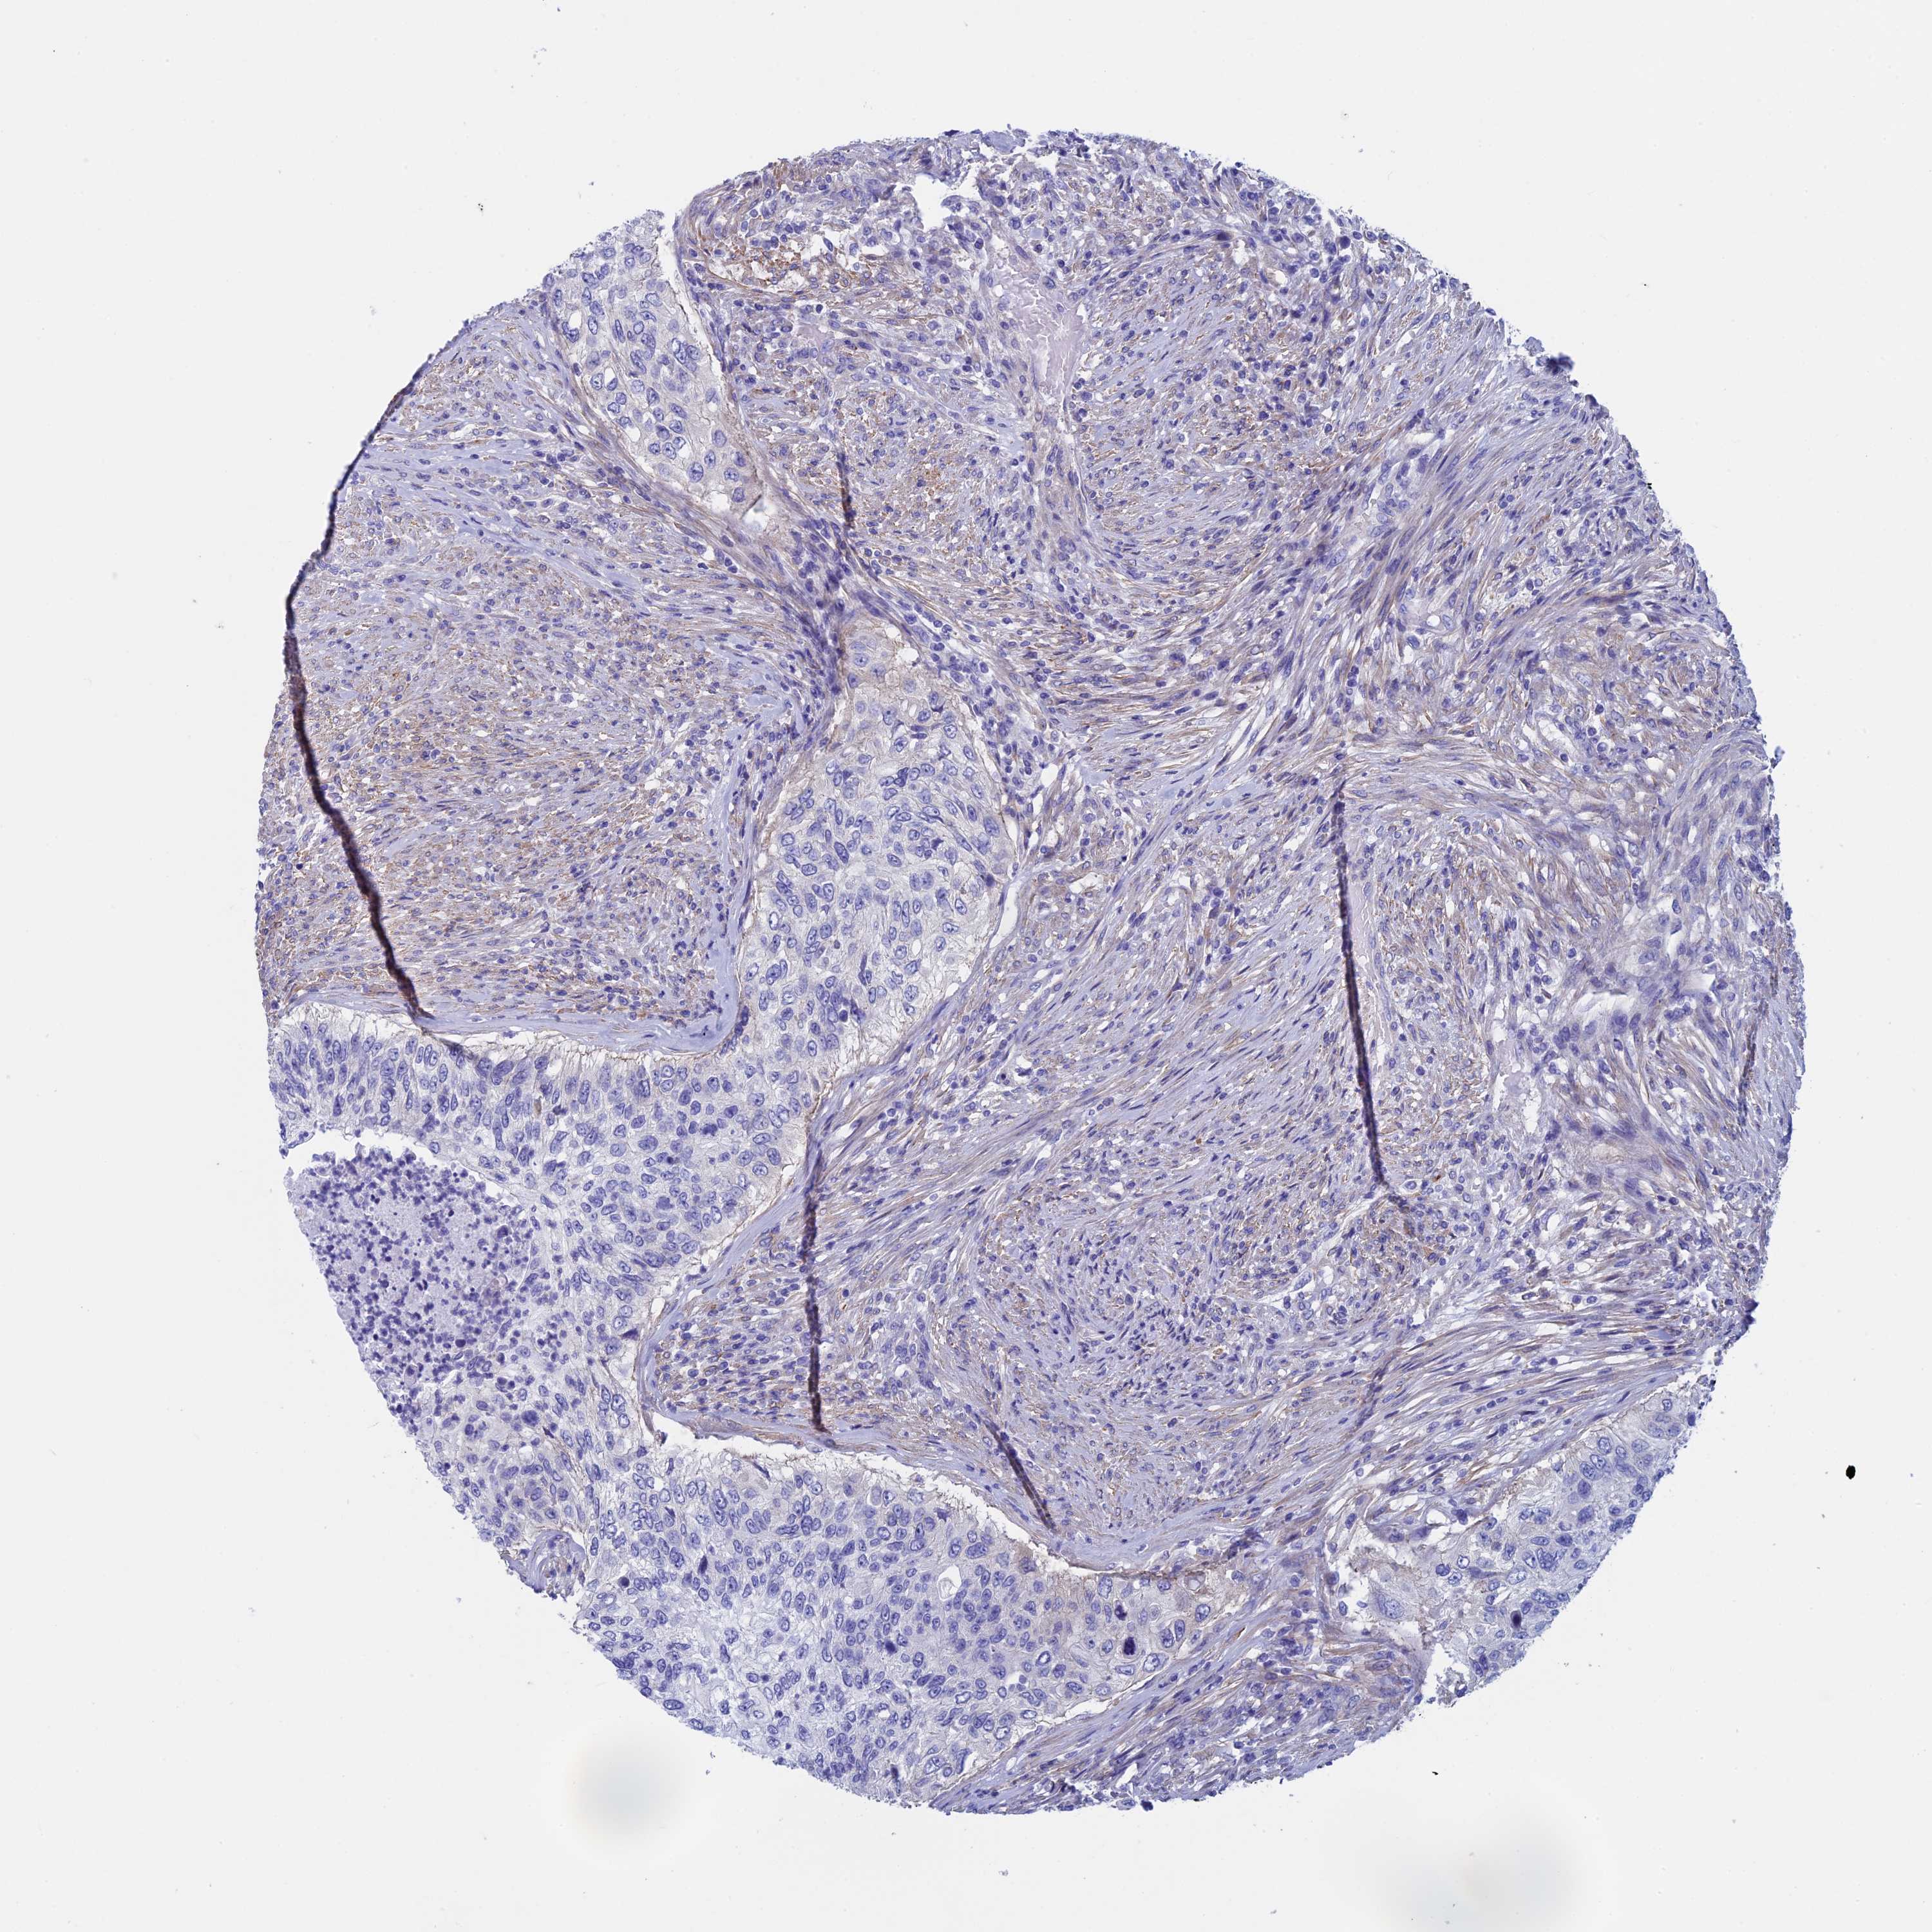

UROTHELIAL CANCER - Protein expressioni

A mouse-over function shows sample information and annotation data. Click on an image to view it in a full screen mode. Samples can be filtered based on level of antibody staining by selecting one or several of the following categories: high, medium, low and not detected. The assay and annotation is described here.

Note that samples used for immunohistochemistry by the Human Protein Atlas do not correspond to samples in the TCGA dataset.

Antibody stainingi

Antibody staining in the annotated cell types in the current human tissue is reported as not detected, low, medium, or high, based on conventional immunohistochemistry profiling in selected tissues. This score is based on the combination of the staining intensity and fraction of stained cells.

Each image is clickable and will lead to virtual microscopy that enables deeper exploration of all samples and also displays staining intensity scores, fraction scores and subcellular localization as well as patient and tissue information for each sample.

Antibody HPA039695

Staining

High

Medium

Low

Not detected

Intensity

Strong

Moderate

Weak

Negative

Quantity

>75%

75%-25%

<25%

None

Location

Nuclear

Cytoplasmic/membranous

Cytoplasmic/membranous,nuclear

Urothelial carcinoma, High grade

Urothelial carcinoma, Low grade